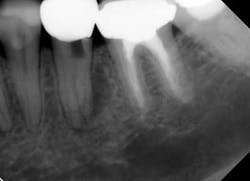

Knowing when a tooth is restorable (and when it is not) is a key diagnostic skill and a predictor of future endodontic success. Taken at face value, this concept seems obvious, but, for example, assessing when a tooth is vertically fractured and/or has a risk of future vertical fracture is not always clear, as is illustrated by the case shown in Fig. 1.